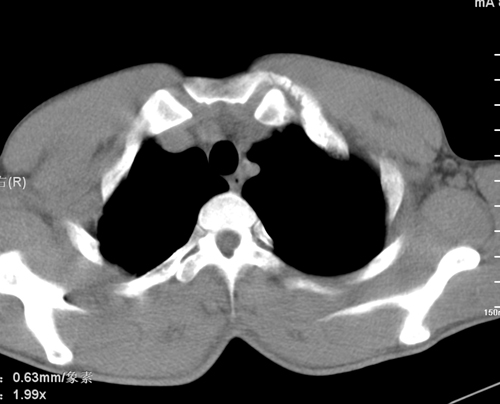

标题: CT24548:男 31 咳嗽 咯血一天 行CT检查 [打印本页]

标题: CT24548:男 31 咳嗽 咯血一天 行CT检查

ct考虑结核 但化验结果示白细胞总数 淋巴均正常,血沉7mm/h不快,请看看结核 支扩还是其他

右肺继发性肺结核伴右肺下叶背段空洞形成。

右肺上叶尖端,后段下叶背段结核伴空洞形成